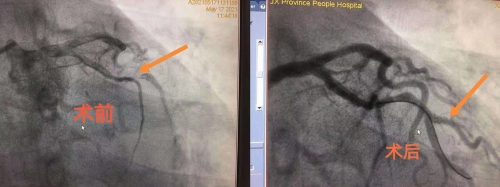

经过实验室检查、心电图检查、影像学检查,欧阳长生将手术目的、过程、风险、可能的预后详细告知患者家属的同时,医护团队立即给患者做好充分的术前准备,并迅速将夏爷爷送入导管室手术。在局麻下行冠状动脉造影,显示多支血管存在狭窄病变,最严重的回旋支中远段长病变,狭窄最重约95%,详细告知家属患者冠脉病变严重情况后,家属表示理解并要求行支架术治疗,立即予开通最严重病变血管,术中顺利,术后患者安返病房,生命体征平稳,右上腹疼痛明显缓解,经过医护团队精心治疗与护理,夏爷爷的病情恢复得很快,患者及家属满怀激动,“感谢欧阳主任及全体医护人员,是你们给了我父亲第二次生命”。